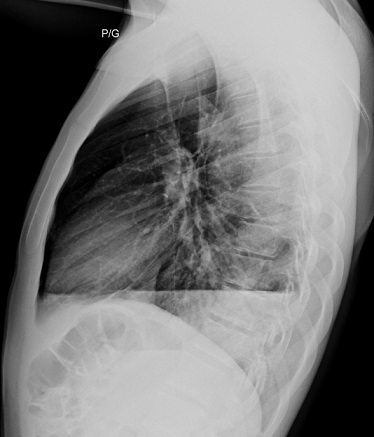

Image

radiologique cliche de face PA d'une pneumothorax du

poumon droit avec aspect de collabe legere du poumon

droit avec de zone peripherique pulmonaire n'a pas

de trame de parenchyme du pomon droit . Il est un

peut de difficile de interpreter et observer

la limite du plevre visceral pulmonaire |

Aspect radiologique de même

cas avec image de collabe du poumon droit , le

mediastin devie vers à gauche . On peut en s'observe

la limite hyperdense de la plevre visceral du poumon

droit tres nette et facilement . Image radiologique

TDM en coupe axial fenetre parenchymateuse |